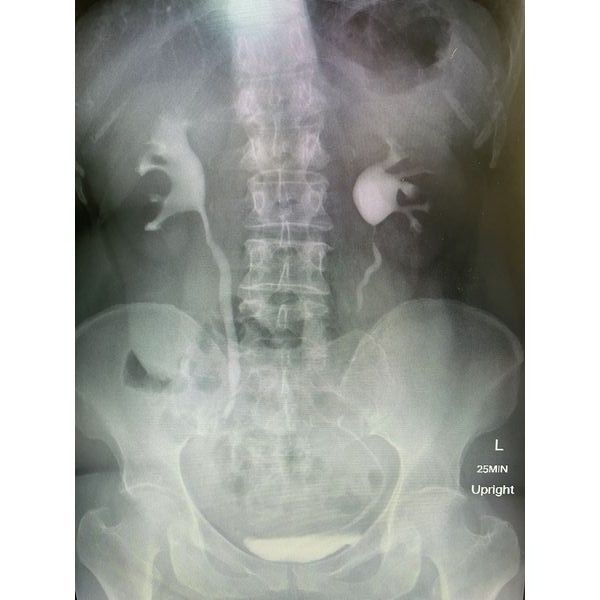

Контрольная обзорная урография показала, что стент не достигал мочевого пузыря и находился в нижней трети мочеточника. Чтобы скорректировать его положение, женщине дополнительно провели цистоскопию и уретероскопию под рентген-контролем: с помощью щипцов конец стента подтянули в мочевой пузырь.

Спустя 5 дней после операции пациентку выписали, через 10 дней ей удалили швы, через 4 недели — мочеточниковый стент.